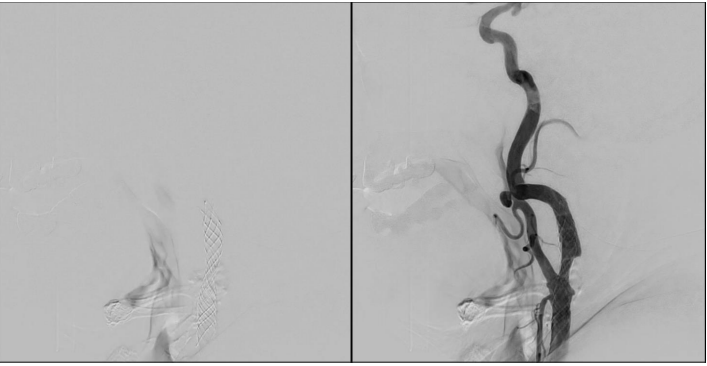

② 経皮的頚動脈ステント留置術

カテーテルを用いた治療です。足の付け根の血管(大腿動脈)から太いカテーテルを挿入し、大動脈を経由して、首の動脈(総頚動脈)までこの太いカテーテルをもっていきます。この太いカテーテルを通して、細くなった血管にバルーンがついたカテーテルを通し、バルーンを膨らませて血管を広げます。広げた血管にステントと呼ばれる金網を入れ、再度バルーンを入れて圧着させてます。カテーテルを抜いて、止血デバイスを用いて止血して終了です。

手術前日に入院し、入院翌日に手術を行います。手術当日はナースステーション隣にある重症患者病室で慎重に経過を観察します。帰室してから6時間は仰向けのまま安静が必要です。起き上がったり、立ち上がったりすることは出来ません。翌日朝から歩行、食事を開始し、入院時に入室した病室に戻ります。手術翌日に頭部MRIを行い、脳梗塞など頭蓋内合併症がないか、手術した頚動脈が広がっているかどうか確認します。問題がなければ、術後5日目~1週間後に退院します。入院期間は6~9日間です。